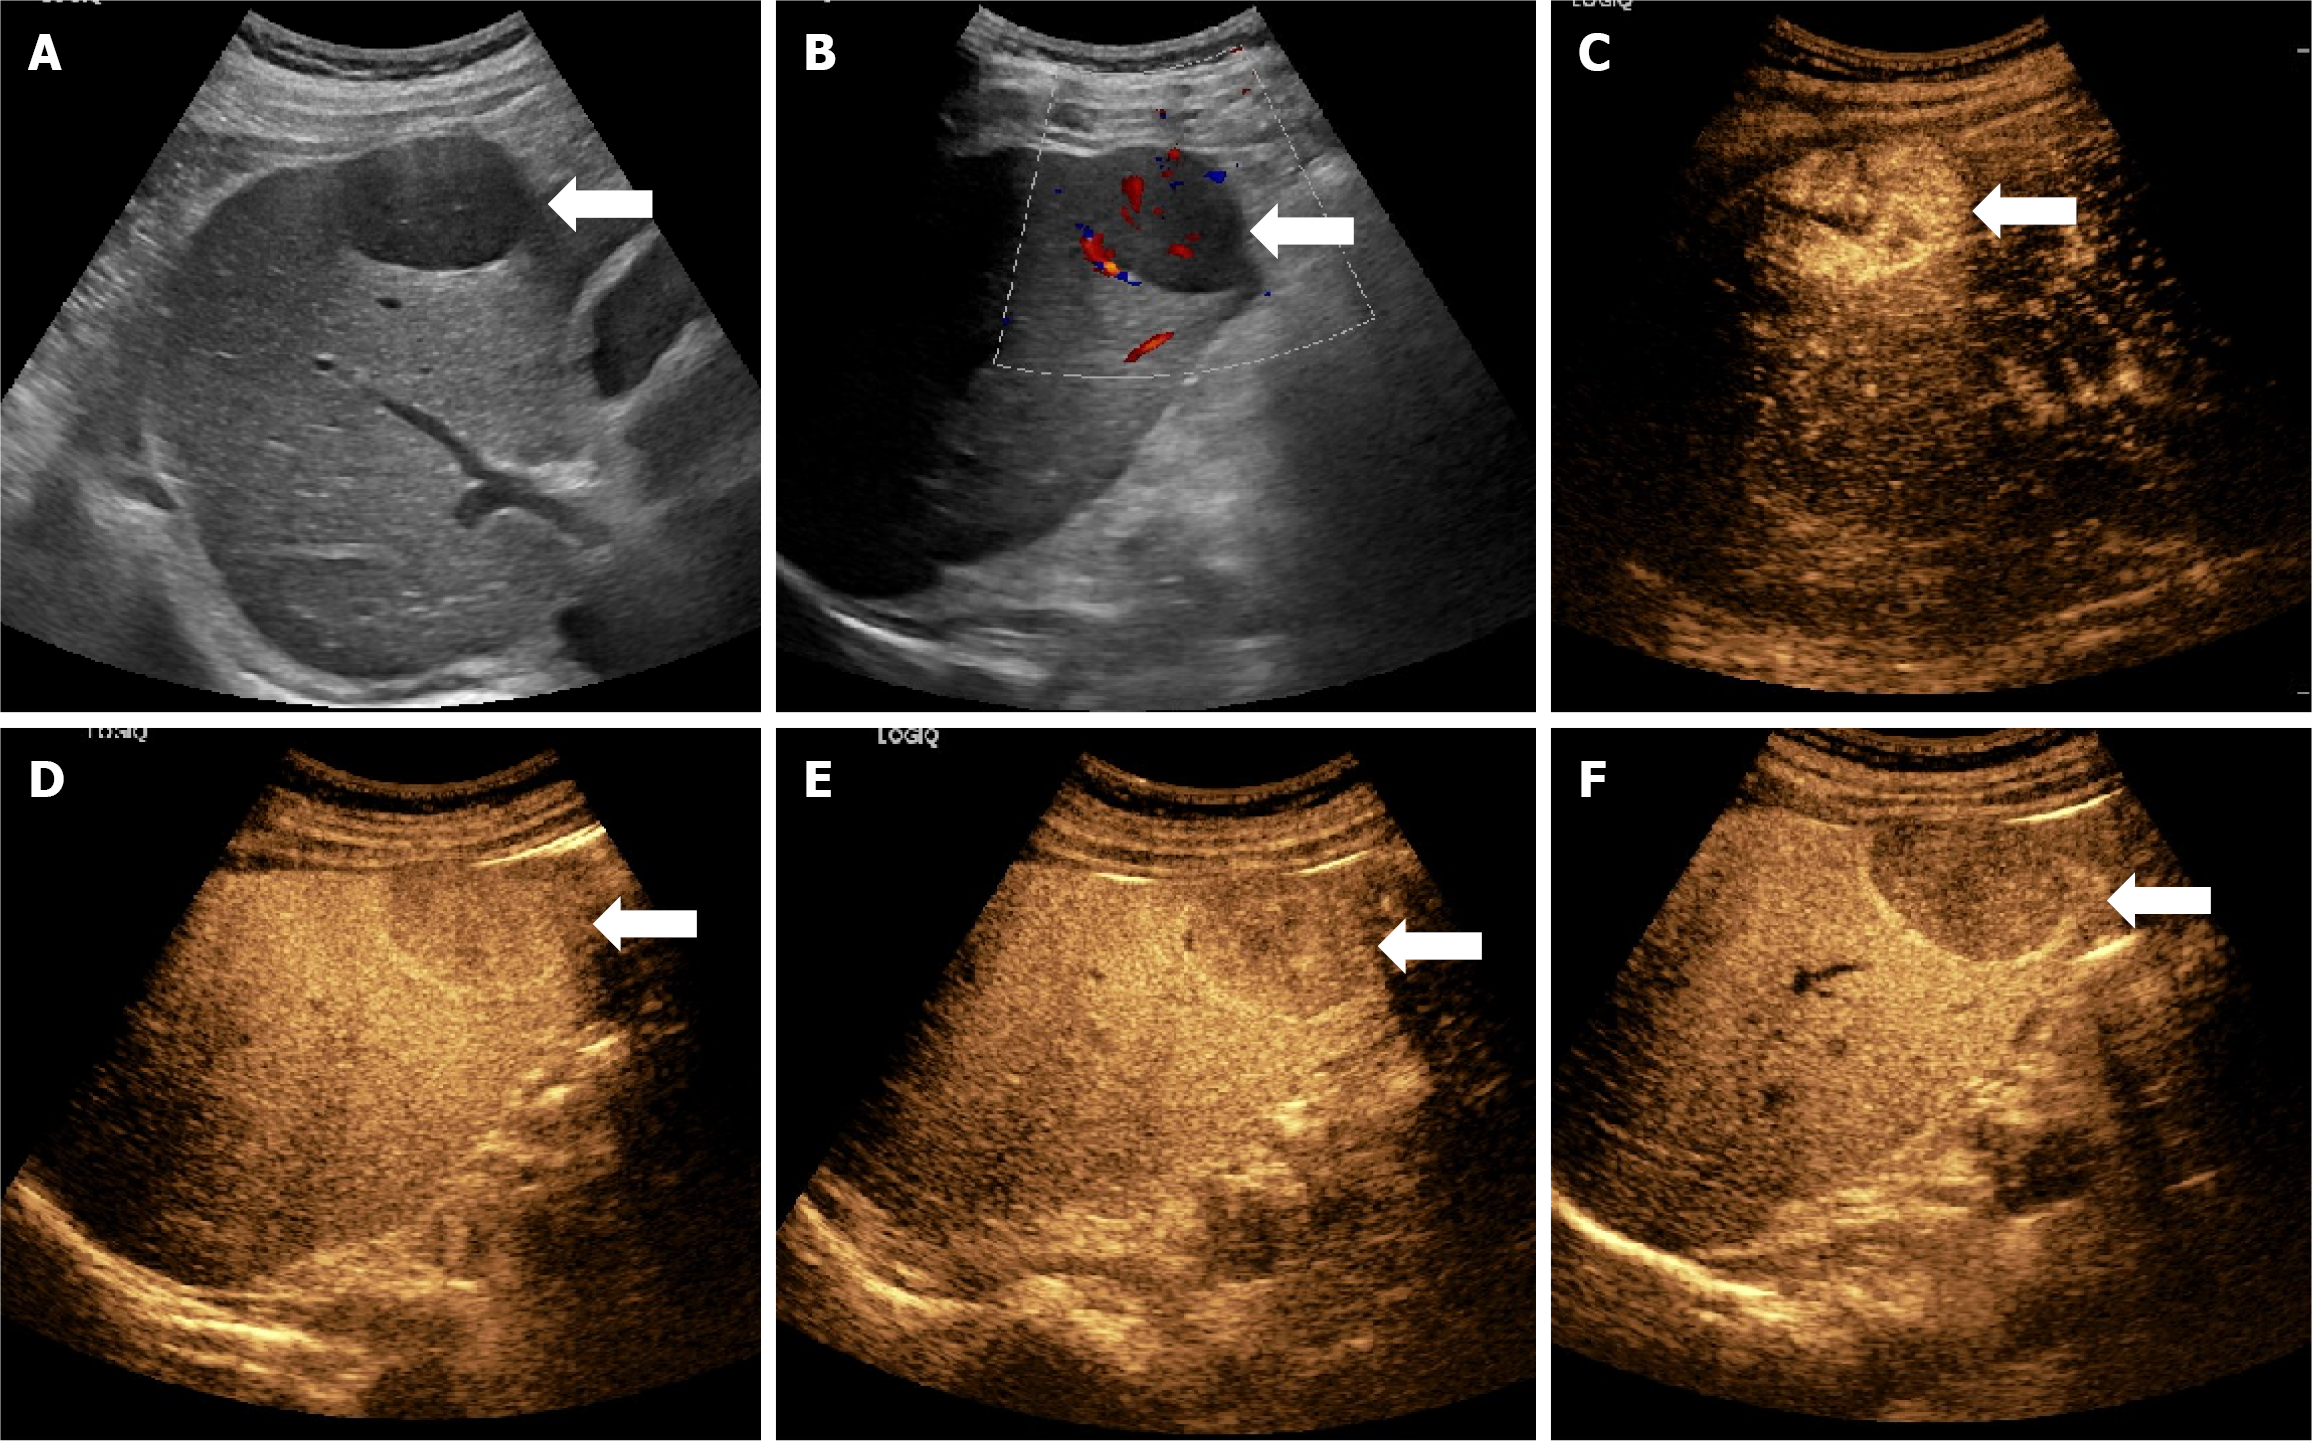

Figure 2 Ultrasound figures of a case of poorly differentiated hepatocellular carcinoma.

The figure presents the case of a 50-year-old male patient without chronic hepatitis B, in whom a liver mass was revealed as poorly differentiated hepatocellular carcinoma with vascular invasion, and a Ki-67 expression of about 50%. A: An ultrasound image showing a mass approximately 3.1 cm in diameter located in the right lobe of the liver; B: Ultrasound image showed abundant short linear blood flow signals in the lesion; C-F: Sonazoid-contrast-enhanced ultrasonography images showing a rapid enhancement of the mass in arterial phase and early washout in the following three phases.